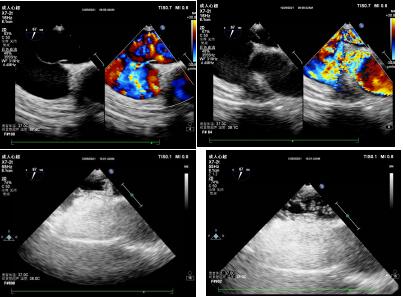

检查前,超声科医师充分了解两位患者基本情况,综合评估患者条件。患者1,女性,31岁,因头痛数年,加重4天就诊,门诊行经颅多普勒发泡实验阳性,为排除心脏疾患,行经食管超声心动图检查。患者2,女性,42岁,因头痛头晕数年,经胸超声心动图提示房间隔瘤形成,为进一步明确诊断,行经食管超声心动图检查。

患者1